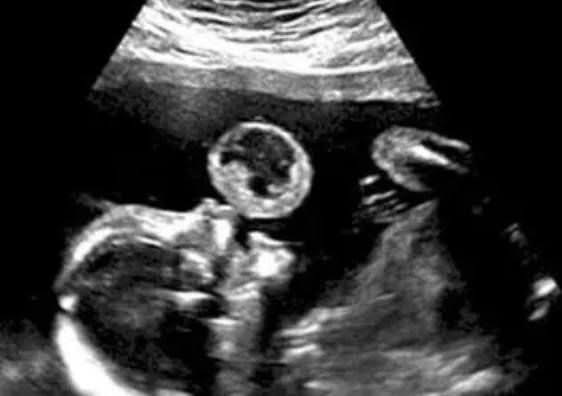

Tammy Gonzalez, of Miami, Florida, was undergoing the routine procedure when doctors reportedly spotted what appeared to be a giant bubble being blown just above the baby’s mouth.

After further inspection, the doctors realized the amorphous bubble was something called a teratoma. Teratomas are extremely rare and usually fatal tumors that affect roughly 1 in every 100,000 births, Diply notes. Gonzalez’s doctors reportedly recommended she terminate the pregnancy lest she face a potential miscarriage.